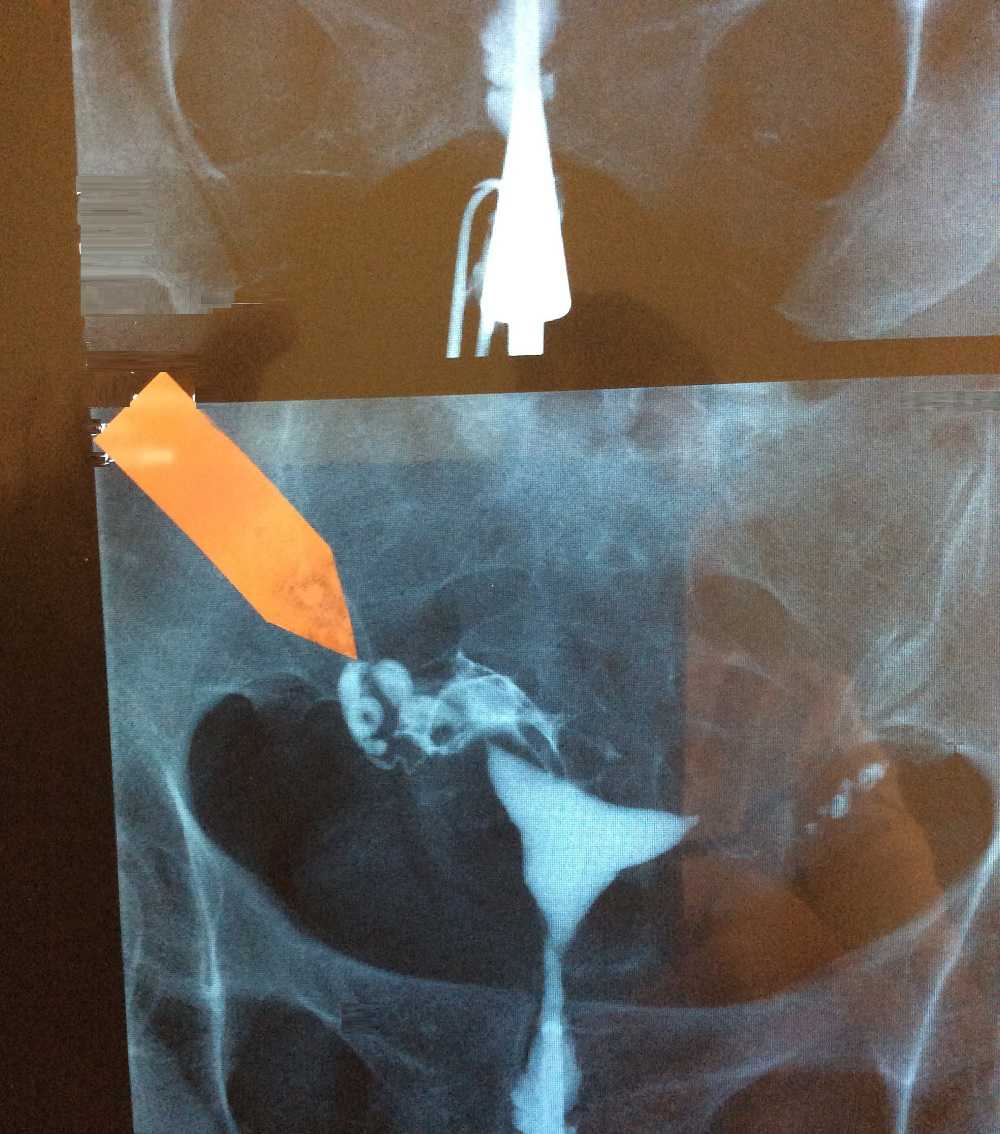

Медицинские снимки: Проходимость маточных труб